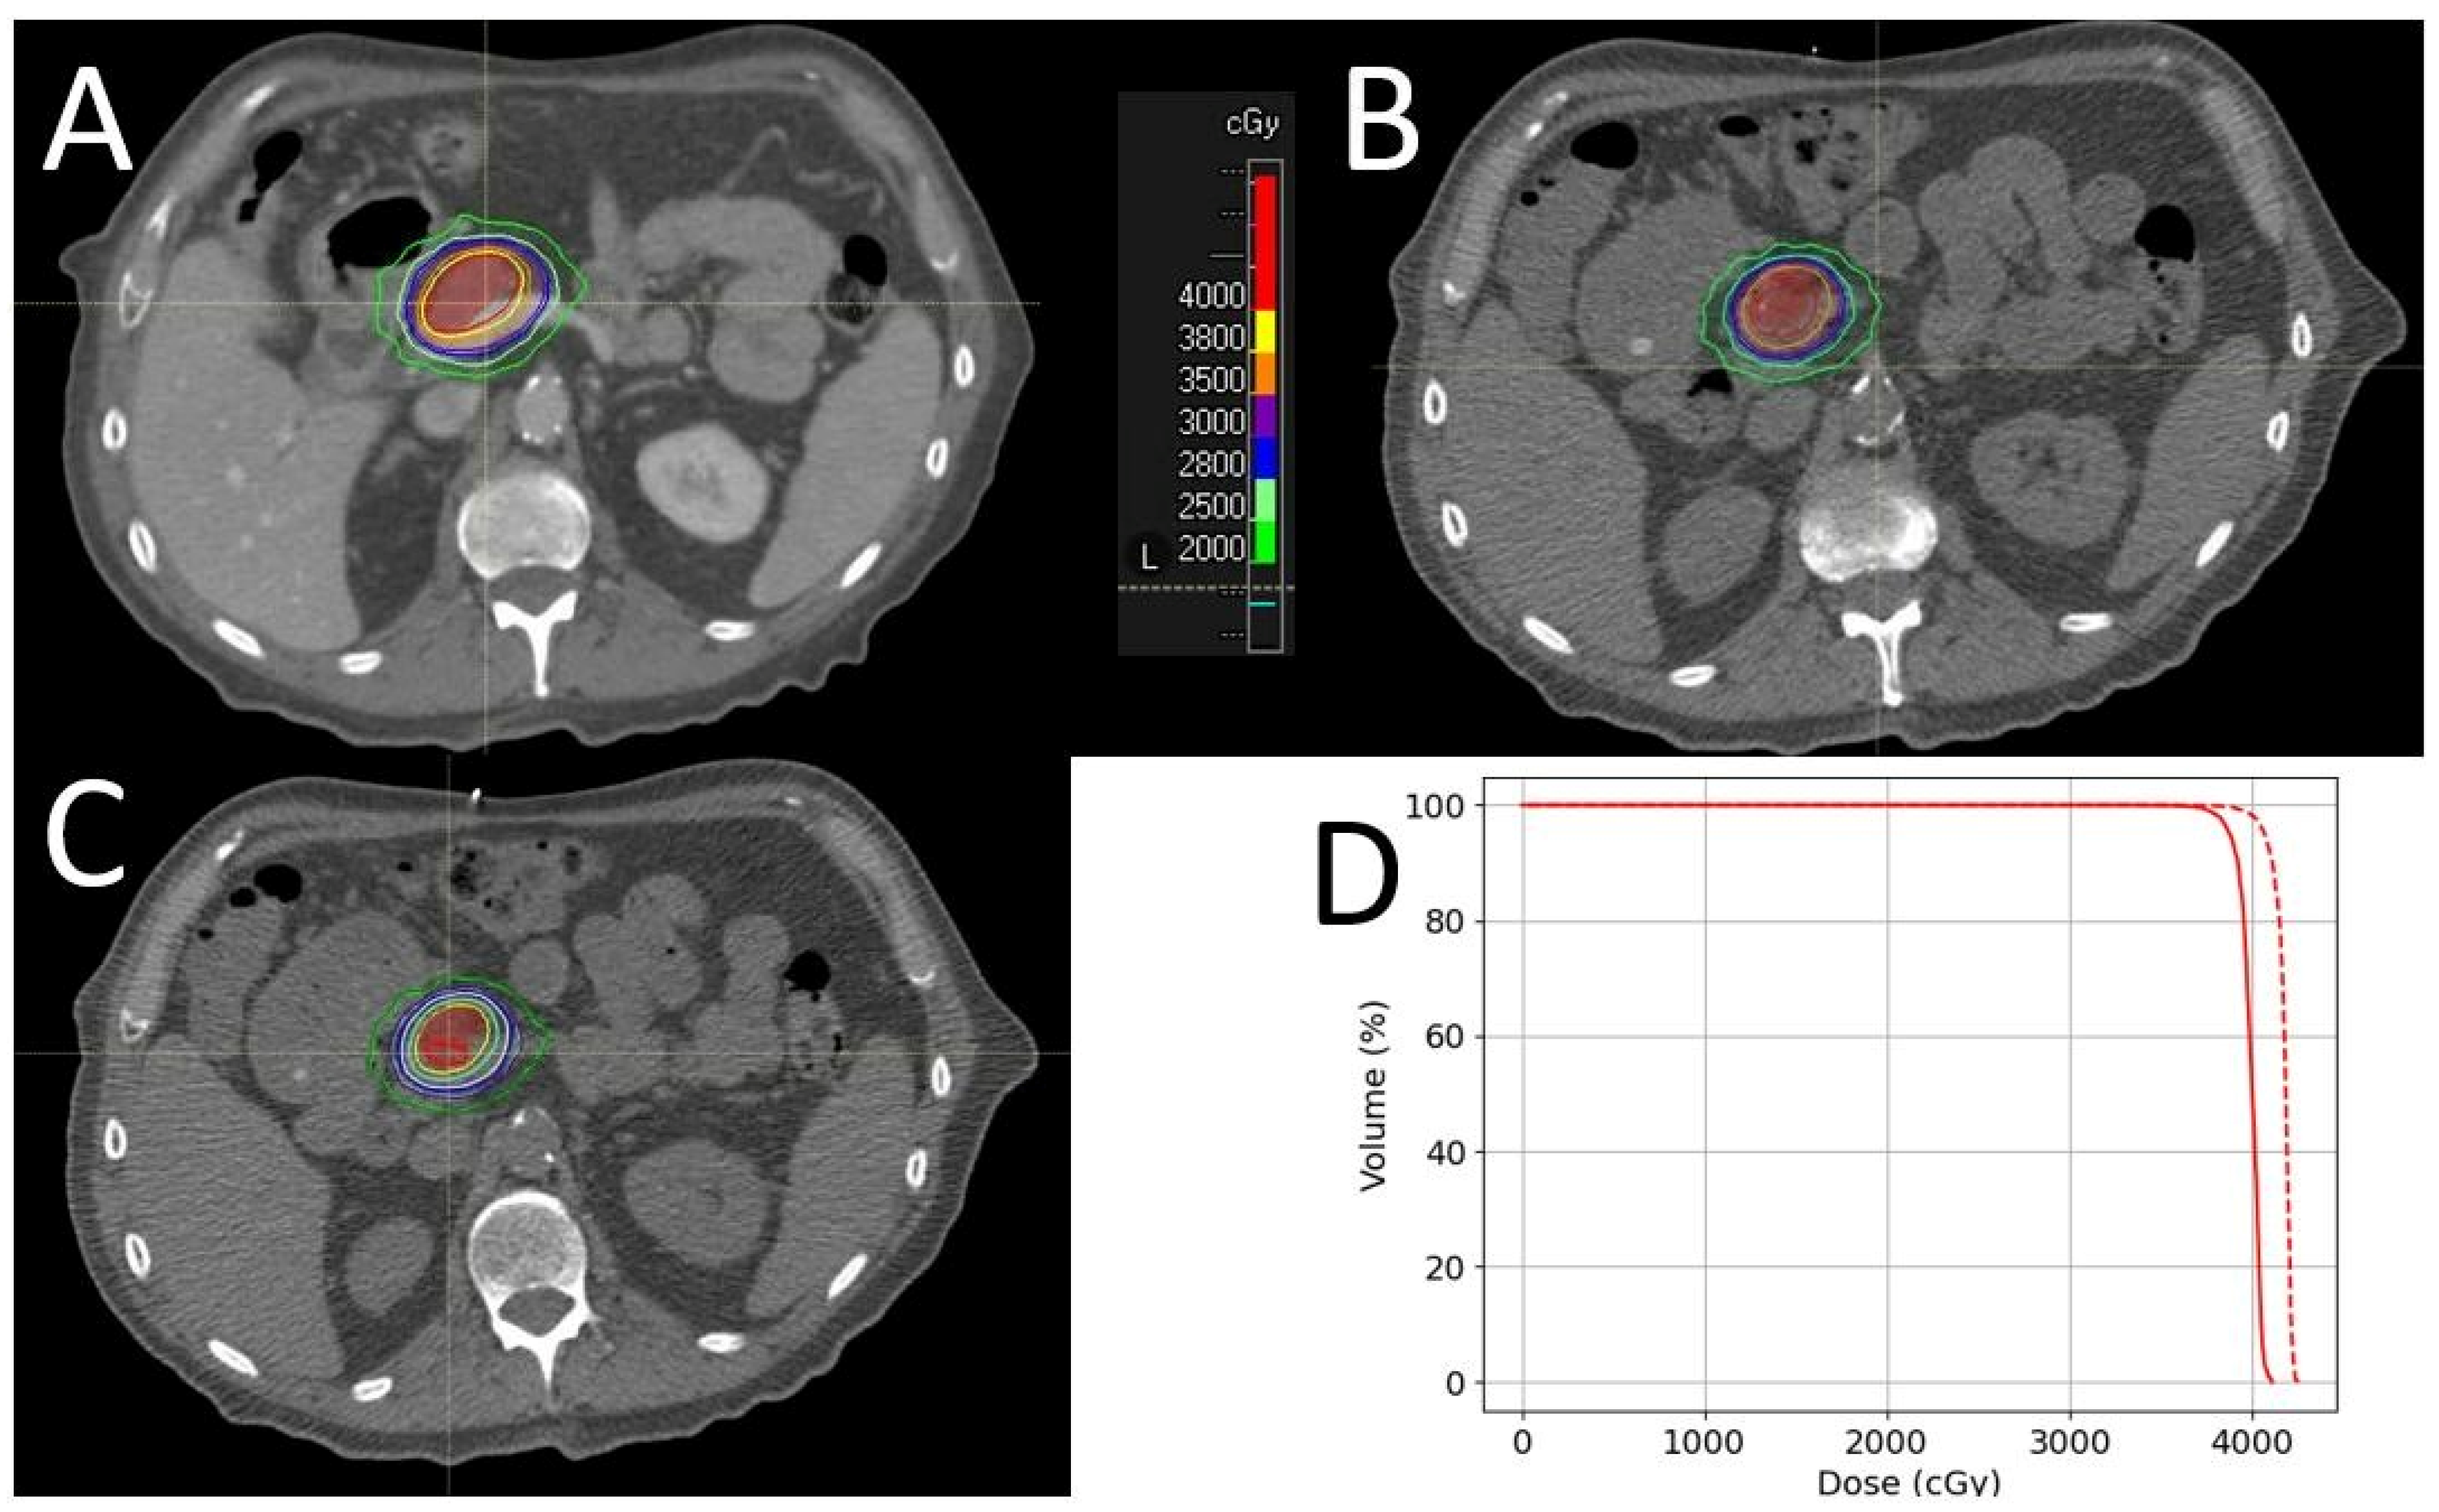

3.3. Case Study 3